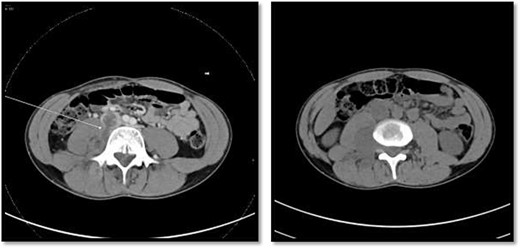

CT scan showed there is 4 × 3 cm lobulated mass noted at the right paravertebral space invading the right psoas muscle at the level of L3 and L4 and extending through the neural foramina, the associated with epidural component compressing the spinal cord from the level of the L2–L4.

An 18-year-old healthy man presented to the emergency department (ED) with 1-day history of right testicular pain and vomiting with no fever nor abdominal pain. Physical examination showed mild tenderness in the right testis, no swelling, normal longitudinal position and cremasteric reflex. Scrotal Doppler ultrasound was performed and showed reduced vascularity in the right testis and the left testis was normal. Moreover, the size and echogenicity were maintained for both testes (Fig. 1). Two months prior to this presentation, the patient presented with the same attack with only mild tenderness in the right testis, and all investigations were within normal limits and he was discharged with oral analgesic drugs. The decision was made to undergo surgical exploration for possible torsion/detorsion of the right testis. The patient was transferred immediately to the operating room for bilateral orchiopexy. The right spermatic cord was engorged with no evidence of ischemia identified and bilateral orchiopexy was done successfully. After the surgery, the patient was kept for observation for 24 h and then discharged. After 2 days from the surgery, the patient came back to ED with testicular pain and post-surgical swelling. We decided to do computerized tomography (CT) scan of the abdominal and pelvis to rule out retroperitoneal pathologies or referred pain. The CT showed 4 × 3 cm lobulated mass noted at right paravertebral space invading the right psoas muscle at the level of L3 and L4 (Fig. 2). The CT scan also showed there is an associated fistula tract between the mass and infrarenal inferior vena cava with thrombosis associated with epidural component extending through the neural foramina compressing the spinal cord from the level of the L2–L4 (Fig. 3). The patient was referred to spinal surgery and CT-guided paraspinal lumbar biopsy was taken. The histopathology came with the diagnosis of Ewing sarcoma. The decision was made by the medical oncology to start on a systemic chemotherapy (vincristine + Adriamycin + cyclophosphamide alternating with ifosfamide + etoposide (VAC/IE)) regimen. After six cycles, the follow-up magnetic resonance imaging demonstrated significant resolution of the right psoas and posterior paraspinal metastatic disease. In addition, further resolution with residual intraspinal extradural metastatic disease noted at right L2–3 and L3–4 levels. The patient is still followed up as an outpatient clinic with medical oncology.

On the left image, there is associated fistulas tract between the mass and infrarenal inferior vena cava with a small hyperdense component may represent hemorrhage or solid component. The right image CT scan showed the mass extending through the neural foramina compressing the spinal cord from the level of the L2–L4.